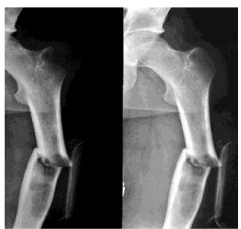

Oberarmbruch - Subcapital

Nagel soll Position fixieren und Knochen zum heilen bringen

mit vielen, zielgerichteten Schrauben Knochen an richtigen Platz bringen

Oberarmfraktur

Schaft & distales Ende - einfach

Druck ist wichtig